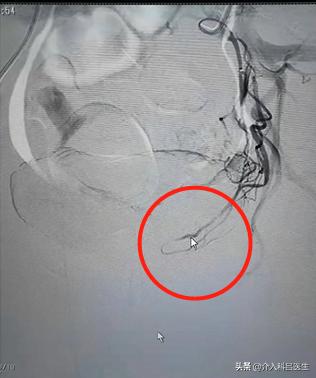

这样,因为 子宫内的环境没有改变,小的肌瘤得到了更多养分,就会长大,这就又复发了。赵女士复发之后,医院给的建议就是切除子宫,这样确实根治了,没有子宫了怎么长肌瘤?但是肯定是不舍得的,子宫不是阑尾说切就切了,这样重要的一个性器官,大多人是狠不下心去切除的。我们介入科,介入栓塞治疗的原理是什么?所有的肌瘤它连着两根血管,这两根血管给它栓塞,在这种情况下,不管子宫上有多少肌瘤,三五个也好,十个八个也好,所有的肌瘤都得不到营养。没有营养肌瘤就会“饿死了”,慢慢慢慢吸收掉。